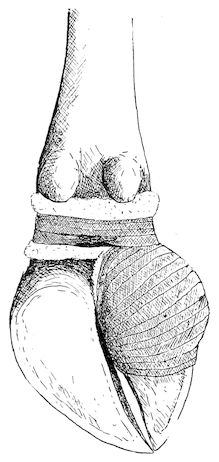

Fig. 1.—Rachitis in a young goat.

Fig. 1.—Rachitis in a young goat.